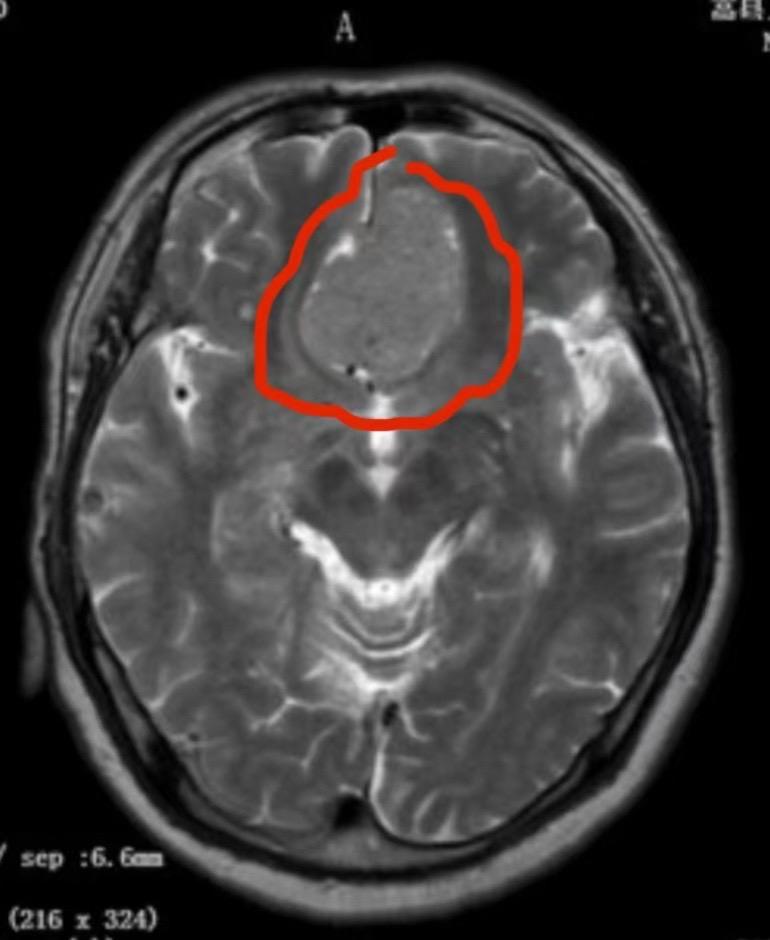

脑室内脑膜瘤也是良性肿瘤。49岁朝鲜族女性,在韩国工作,因头痛、呕吐发...